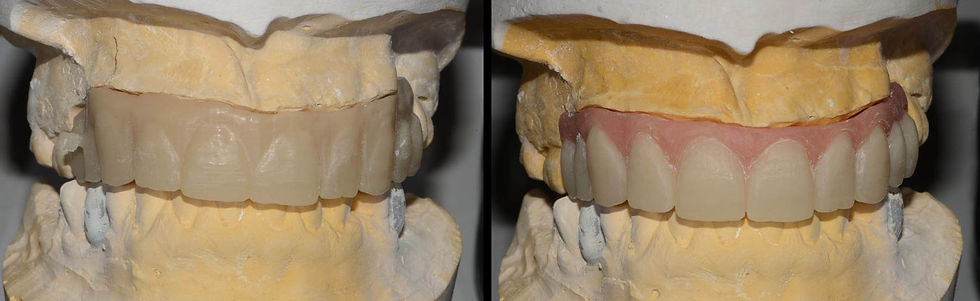

PMMA temporary prosthesis obtained with CAD-CAM technology.

On the temporary prosthesis it is possible to remove material in the area of the prosthetic flange and fill with palate resin for mobile prosthesis.

After 4 months, once the osseointegration of the loaded and unloaded implants is verified, definitive impressions are taken. An hybrid metal-ceramic prosthesis is made with synthetic tissue to replace the orthopedic component of the restoration, well integrated into the patient’s facial context.